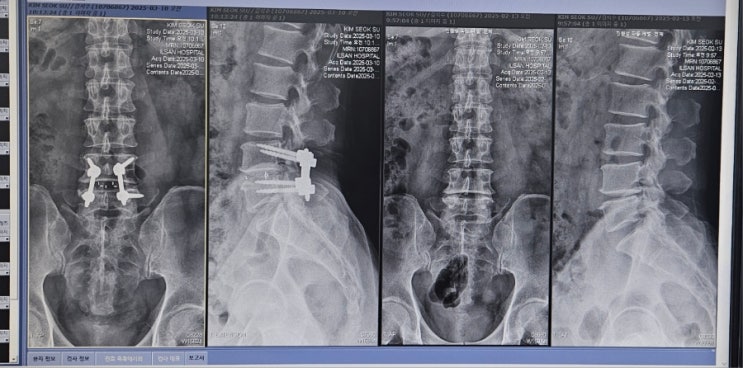

재활 3주차 (3.9~3.15)

재활3주차 ☆ 증상 - 허리통증 수술부위 열감, 붓기, 틍증약간 - 우측방사통은 없으나 엉치부근 통증 - 우...